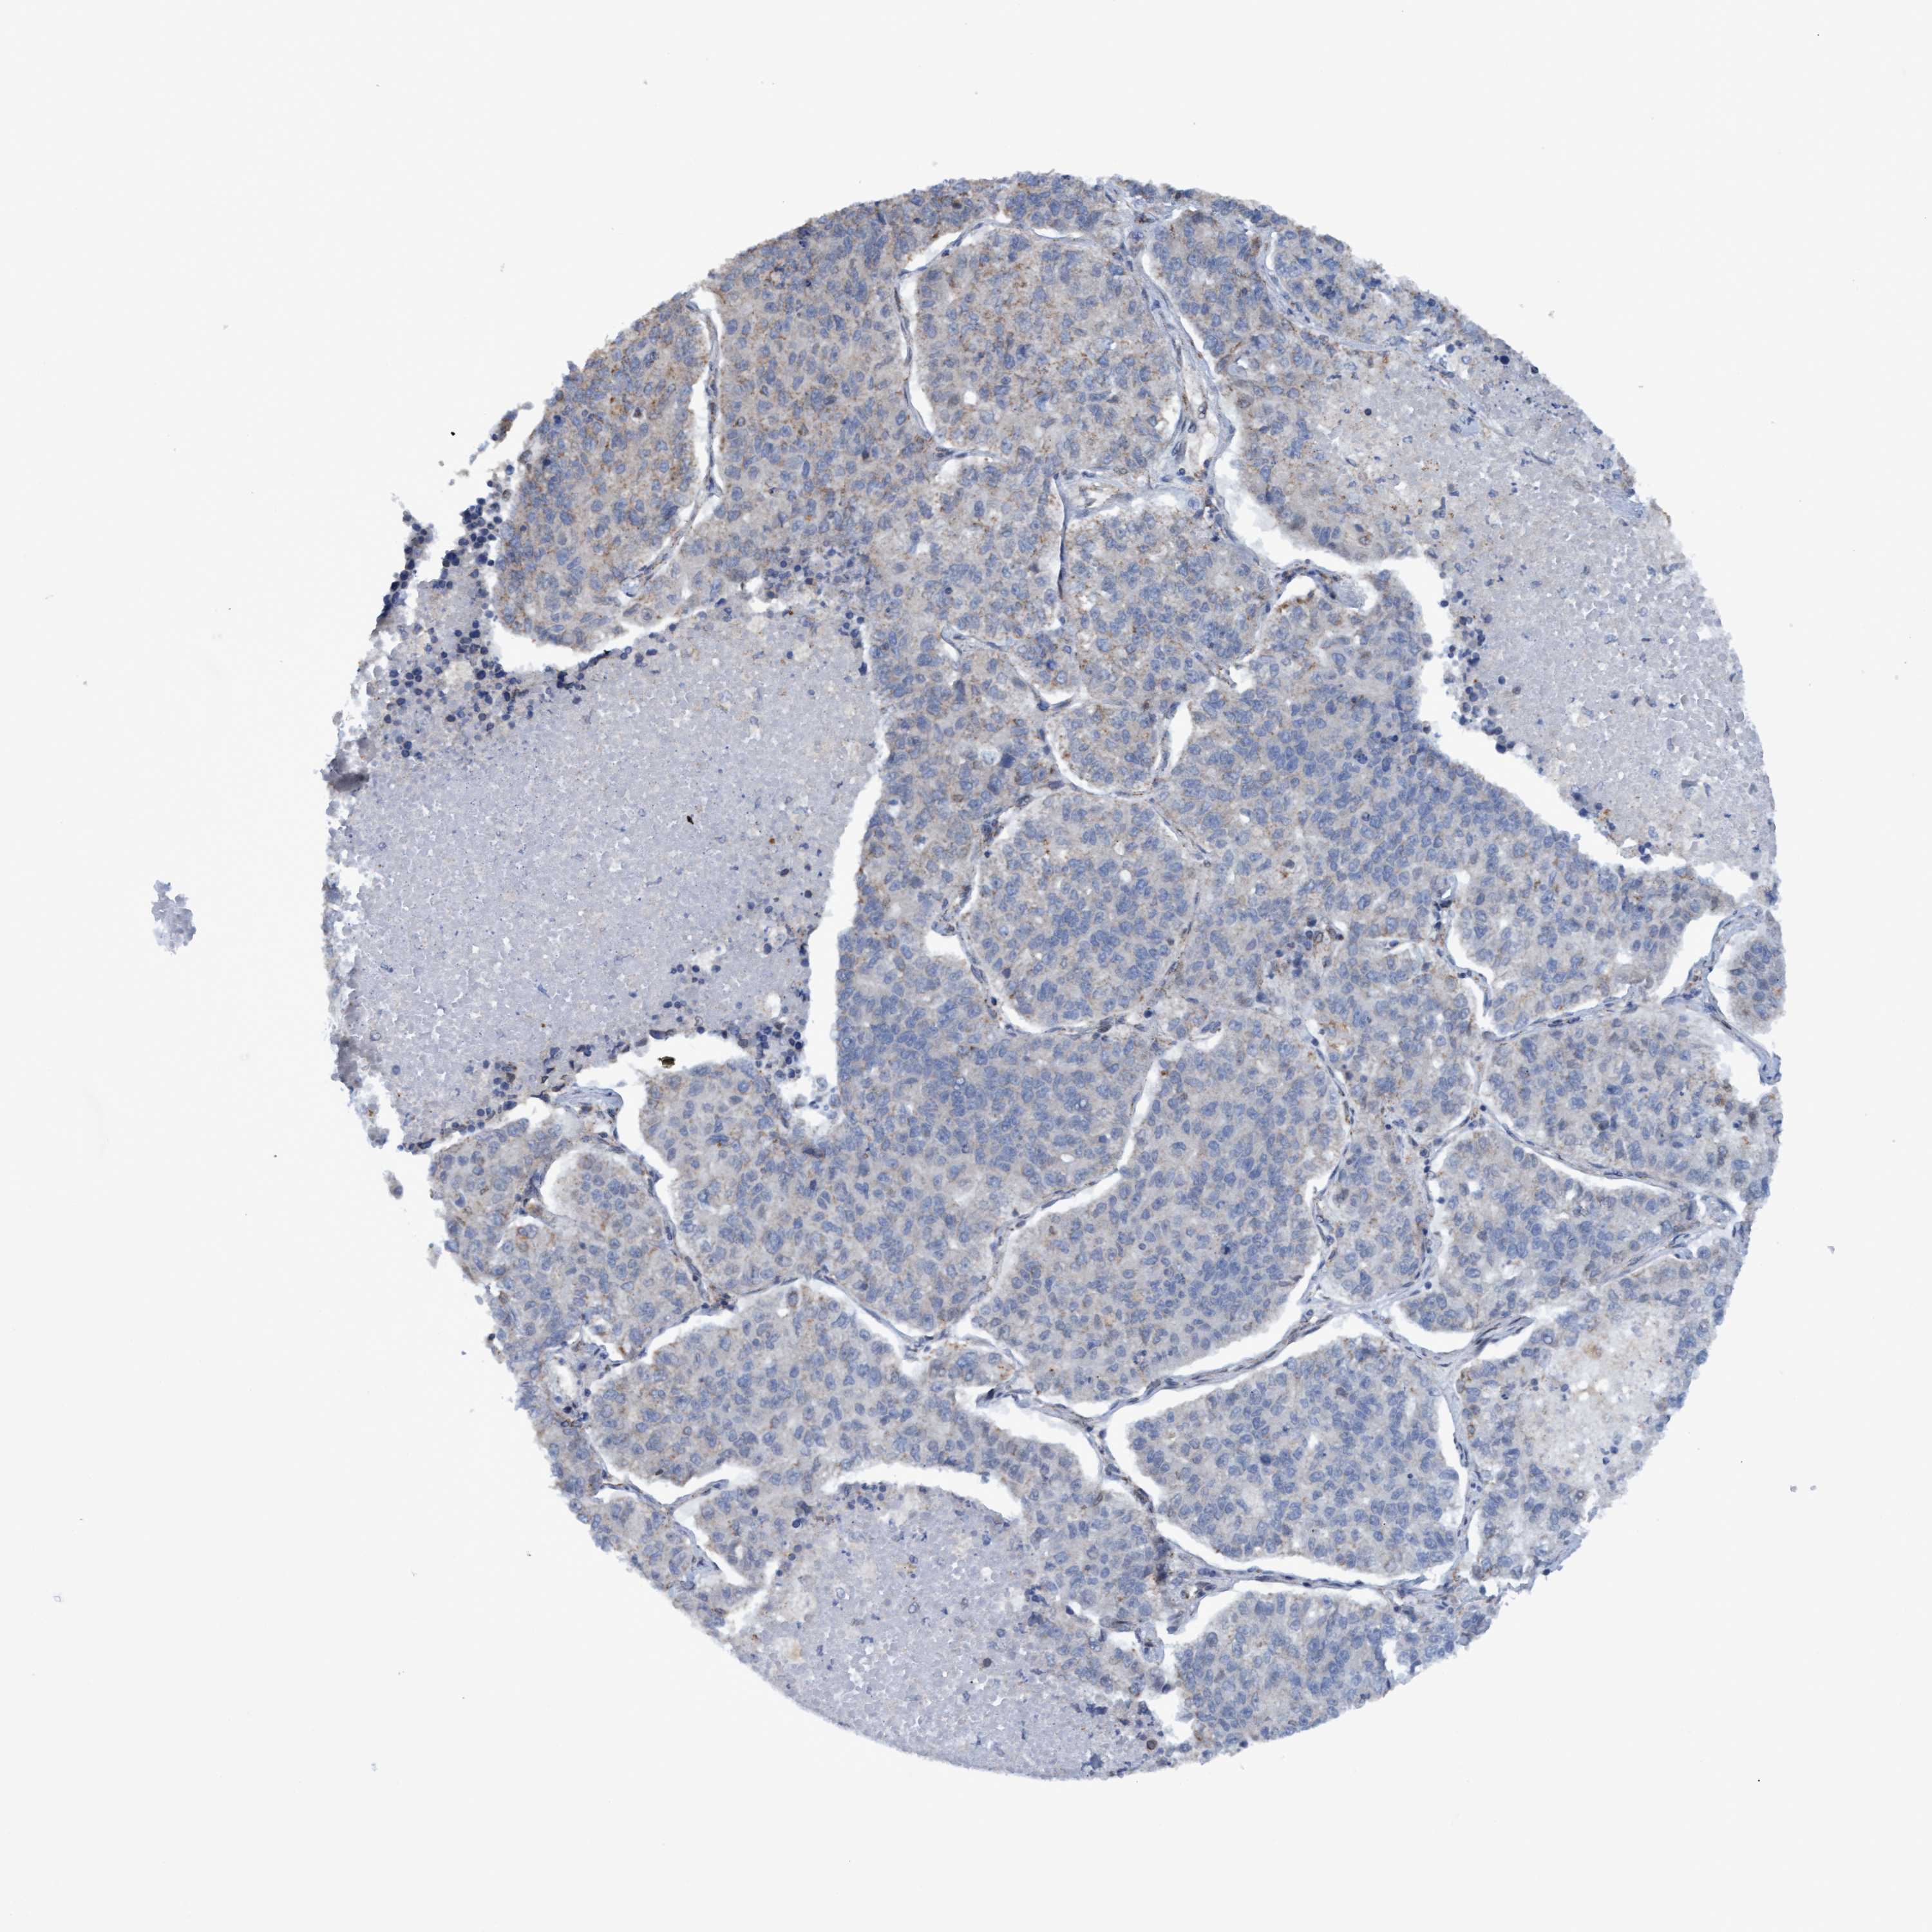

LUNG CANCER